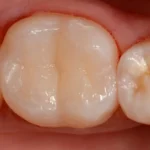

Antigamente, restaurações com amálgama de prata eram muito utilizadas nos tratamentos para cárie. Entretanto, uma de suas desvantagens é o aspecto pouco estético que elas resultam, diferentemente das resinas dentárias que possuem cores próximas aos dentes e proporcionam beleza e naturalidade às restaurações.

Além disso, por ser uma restauração adesiva, a resina apresenta maior biocompatibilidade.

Confira este caso clínico de restauração dentária posterior, terceiro molar, com a resina tipo Bulk da 3M.